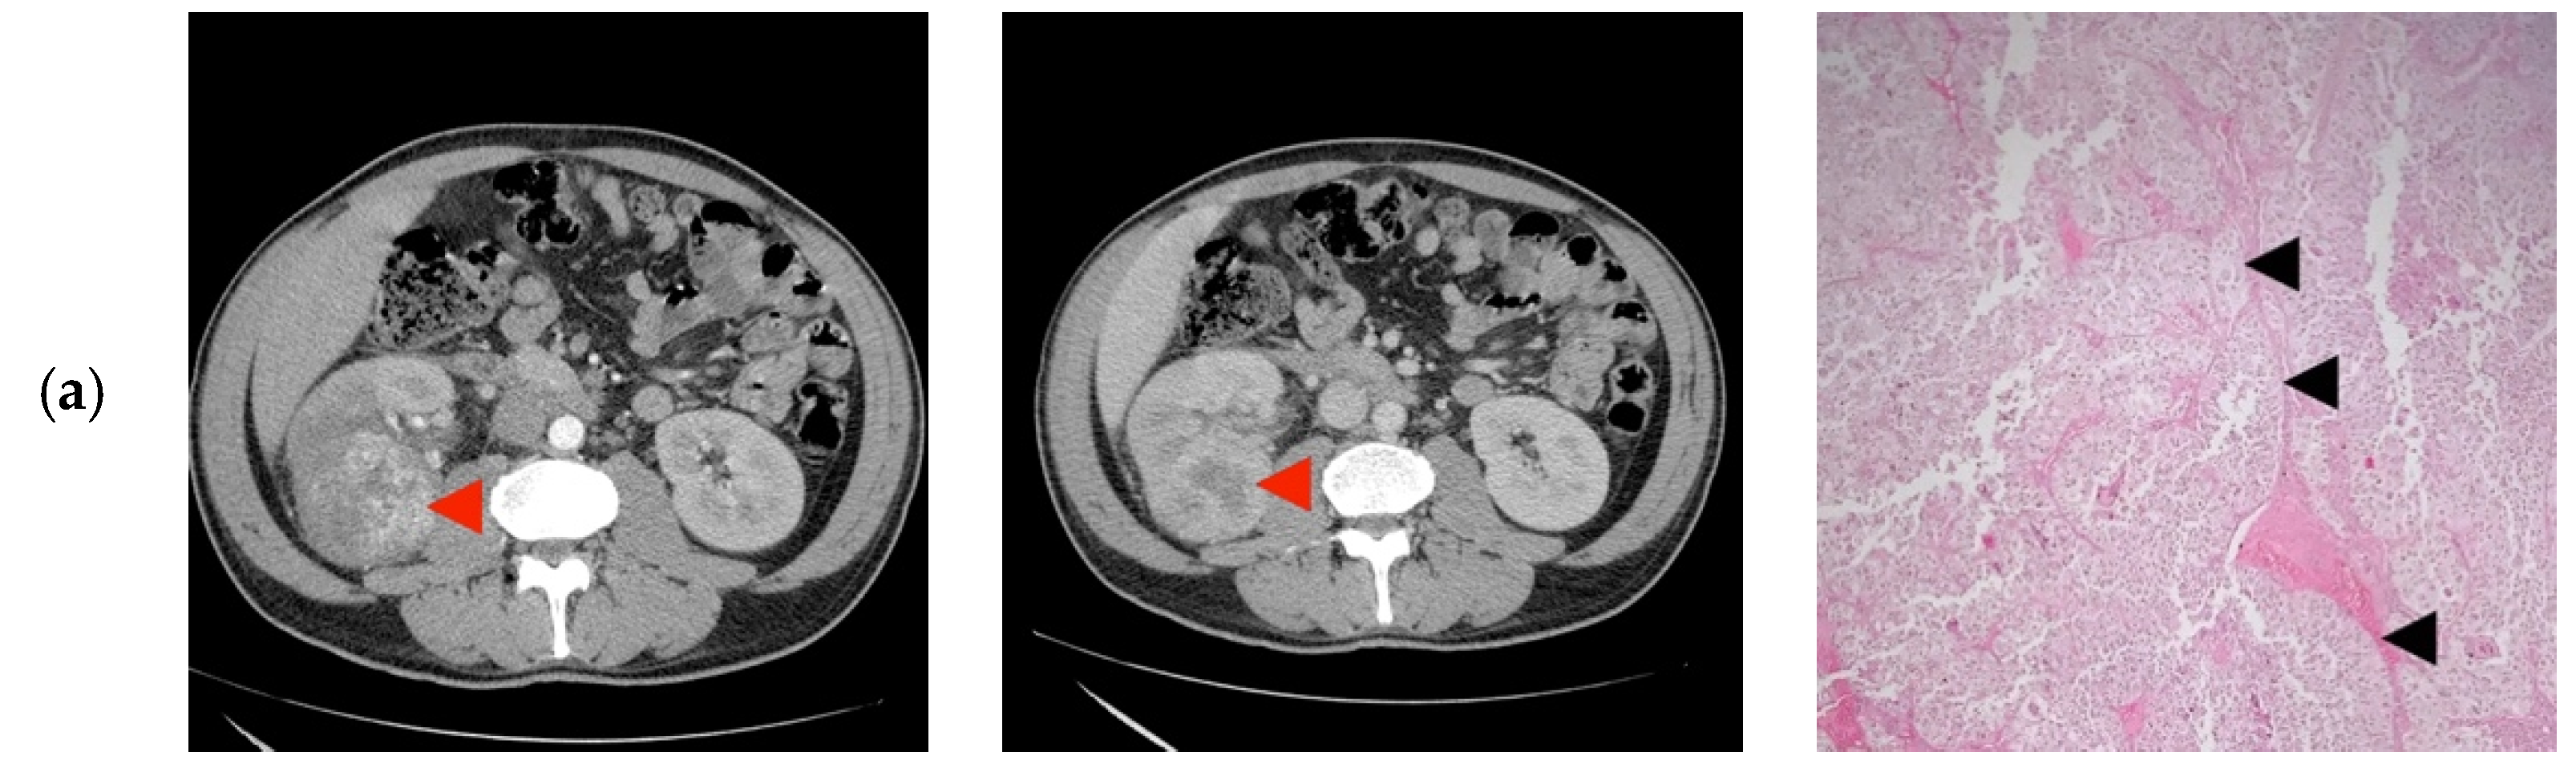

| 1 | 45/M | cT2N0 | 73 | 9 | Clear Cell RCC |

| 2 | 27/F | cT1bN0 | 60 | 8 | Clear Cell RCC |

| 3 | 38/M | cT1bN0 | 47 | 10 | Papillary/Clear Cell RCC Oncocytoma |

| 4 | 24/M | cT2N0 | 85 | 10 | Clear Cell RCC |

| 5 | 31/F | cT1aN0 | 35 | 8 | Papillary Clear Cell RCC |

| 6 | 41/M | cT2N0 | 86 | 10 | Clear Cell RCC |

| 7 | 29/M | cT1bN0 | 40 | 8 | Oncocytoma |

| 8 | 30/F | cT1bN0 | 44 | 10 | Papillary/Clear Cell RCC |

| 9 | 32/F | cT1bN0 | 52 | 11 | Clear Cell RCC |

| 10 | 25/M | cT1bN0 | 45 | 11 | Papillary/Clear Cell RCC Complicated cyst Oncocytoma/Fat poor AML |

| 11 | 43/F | cT1bN0 | 50 | 9 | Papillary RCC/Oncocytoma Fat poop AML |

| 12 | 41/F | cT2N0 | 73 | 10 | Oncocytoma |

| 13 | 43/M | cT3aN0 | 33 | 7 | Clear Cell RCC |

| 14 | 38/F | cT1bN0 | 50 | 8 | Bleeding Clear Cell RCC |

| 15 | 32/M | cT3aN0 | 55 | 10 | Clear Cell RCC |

| 16 | 37/M | cT2N0 | 93 | 11 | Clear Cell RCC |

| 1 | Retroperitoneoscopic radical nephrectomy | pT2N0 | Clear Cell RCC Furhman 2 | Yes |

| 2 | Open radical nephrectomy | pT1bN0 | Clear Cell RCC Furhman 1 | Yes |

| 3 | Retroperitoneoscopic radical nephrectomy | pT1bN0 | Papillary-RCC, type II | Yes/No |

| 4 | Open Radical nephrectomy | pT2N0 | Cystic Nephroma | No |

| 5 | Retroperitoneoscopic radical nephrectomy | pT1aN0 | Clear Cell RCC Furhman 1 | Yes/No |

| 6 | Open radical nephrectomy | pT2N0 | Clear Cell RCCFurhman 2 | Yes |

| 7 | Open partial nephrectomy with local renal hypothermia and hilar clamping | PT1bN0 | Multicentric Chromophobe-RCC | No |

| 8 | Open partial nephrectomy with local renal hypothermia and hilar clamping | pT1bN0 | Clear Cell RCC Furhman 1 | Yes/No |

| 9 | Retroperitoneoscopic radical nephrectomy | pT1bN0 | Clear Cell RCC Furhman 2 | Yes |

| 10 | Open partial nephrectomy with local renal hypothermia and hilar clamping | pT1bN0 | Multiloculated cystic Clear Cell RCC Furhman 1 | No |

| 11 | Open partial nephrectomy with local renal hypothermia and hilar clamping | pT1bN0 | Metanephric adenofibroma | No |

| 12 | Open radical nephrectomy | pT2N0 | Oncocytoma | Yes |

| 13 | Open partial nephrectomy–segmentary renal vein invasion–radical nephrectomy | pT3aN0 | Clear Cell RCC Furhman 1 | Yes |

| 14 | Open partial nephrectomy with local renal hypothermia and hilar clamping | pT1bN0 | Papillary-RCC, type I | No |

| 15 | Open radical nephrectomy | pT3aN0 | Clear Cell RCC Furhman 1 | Yes |

| 16 | Retroperitoneoscopic radical nephrectomy | pT2N0 | Clear Cell RCC Furhman 1 | Yes |